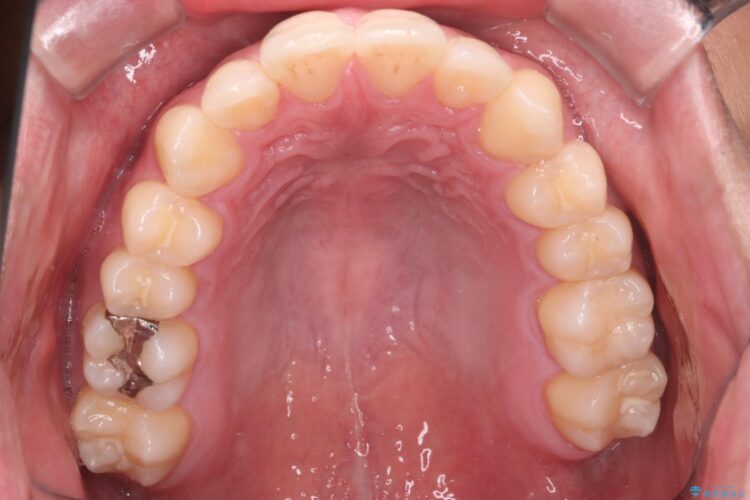

上の前歯が出ているのが気になるとご来院された患者様です。

インビザラインでの治療を希望されました。

IPR(歯と歯の間を削る処置)を行うことで、前歯の位置とがたつき整える治療計画を立てました。